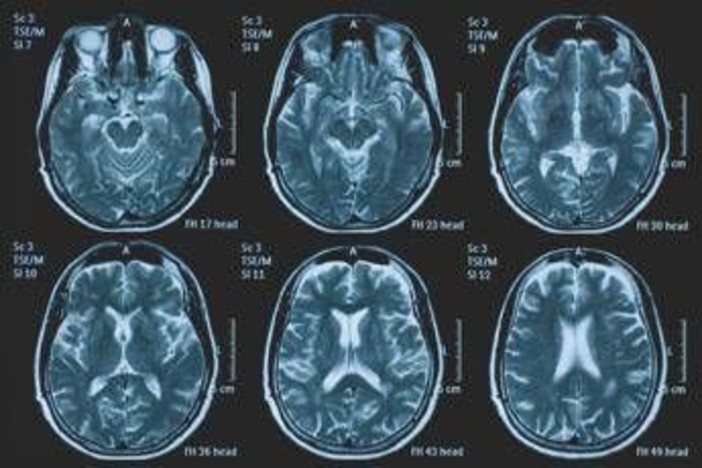

(Adnkronos) - La Commissione europea (Ce) ha autorizzato la commercializzazione condizionata di tovorafenib come monoterapia per il trattamento dei pazienti di età pari o superiore a 6 mesi con glioma pediatrico di basso grado che presentano una fusione o un riarrangiamento del gene Braf o una mutazione Braf-V600, in progressione di malattia dopo una o più terapie sistemiche precedenti. Lo annuncia Ipsen, in una nota, precisando che si tratta della “prima terapia mirata” per questa patologia e che la decisione della Ce si riferisce ai 27 Stati membri della Ue, oltre a Islanda, Liechtenstein e Norvegia. Ogni anno in Ue vengono diagnosticati più di 800 nuovi casi di glioma pediatrico di basso grado (pLgg) con alterazione di Braf. Questo tumore cerebrale, nonostante sia classificato di basso grado (a lenta progressione), comporta un carico significativo e permanente che accompagna la persona per tutta la vita, causando spesso importanti compromissioni fisiche e neurologiche, tra cui perdita della vista, difficoltà di linguaggio e disfunzioni motorie, che possono incidere in modo significativo sull’istruzione, l’autonomia e la qualità di vita a lungo termine del bambino. Finora, molti bambini con pLgg hanno dovuto sottoporsi a interventi chirurgici invasivi, a più cicli di chemioterapia e a radioterapia, con conseguenti complicazioni della salute.